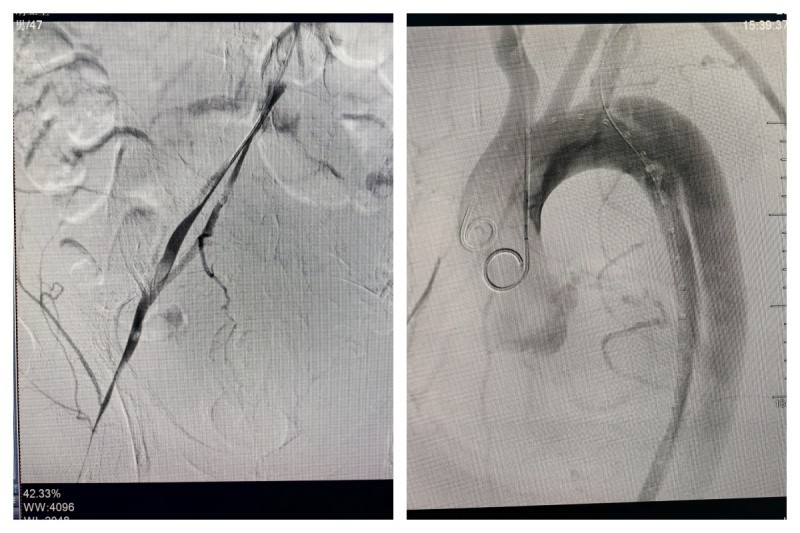

然而,面对如此严峻的挑战,南溪山医院心脏大血管外科的医疗团队并没有退缩。他们迅速为胡某安排了紧急手术。手术中发现,胡某的病情比发病时更为严重。术中造影显示,其主动脉夹层真腔十分细小,左侧髂总动脉闭塞,右侧髂动脉以假腔供血为主。这一情况给手术带来了巨大的困难。

然而,医生们并未退缩,他们凭借着丰富的经验和精湛的技术,另辟蹊径,从上往下成功找到真腔,并顺利完成了手术。在胸主动脉近端置入覆膜支架一枚,覆盖内膜破口;开通闭塞的左髂总动脉并置入支架;右髂动脉细小真腔内也成功置入支架。手术成功封堵住主动脉内膜破口并恢复下肢供血,挽救了胡某的生命并保住了他的下肢。